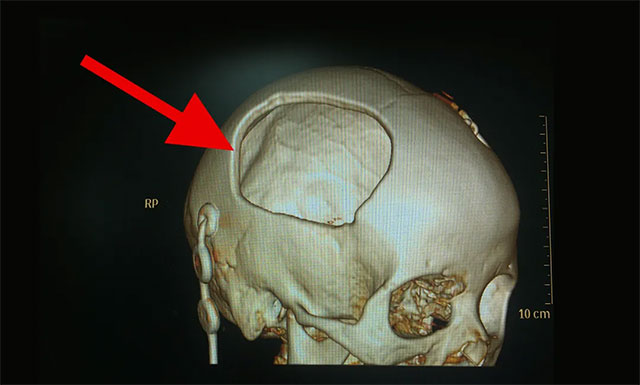

▲ 颅骨大块缺损,脑组织凹陷严重

随后,鉴于患者病情已稳定,其右侧颞顶骨大块缺损,大小约为7厘米X 6厘米,脑组织失去了支撑和保护,且其颅骨缺损的时间愈长,颅骨缺损综合征及继发性脑损害的发生率愈高。因此,今年2月24日对其进行了PEEK颅骨修补术,以便更好地保护脑组织,避免了患者因颅骨缺损而引起的各种健康问题和额外风险。